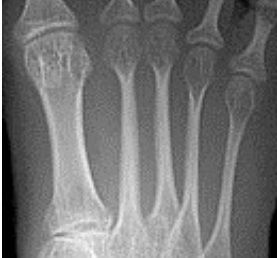

Describe the alignment of metatarsal 2 | There is no angulation nor displacement of the distal segment relative to the proximal segment. |

Describe the alignment of metatarsal 3 | The distal segment is displaced laterally (50% apposition) and angulated medially. |

Describe the alignment of metatarsal 4 | The distal segment is displaced laterally (75% apposition) but there is no apparent angulation. |

Describe the tubulation of the metatarsals | Metatarsals are overtubulated - decreased girth. |